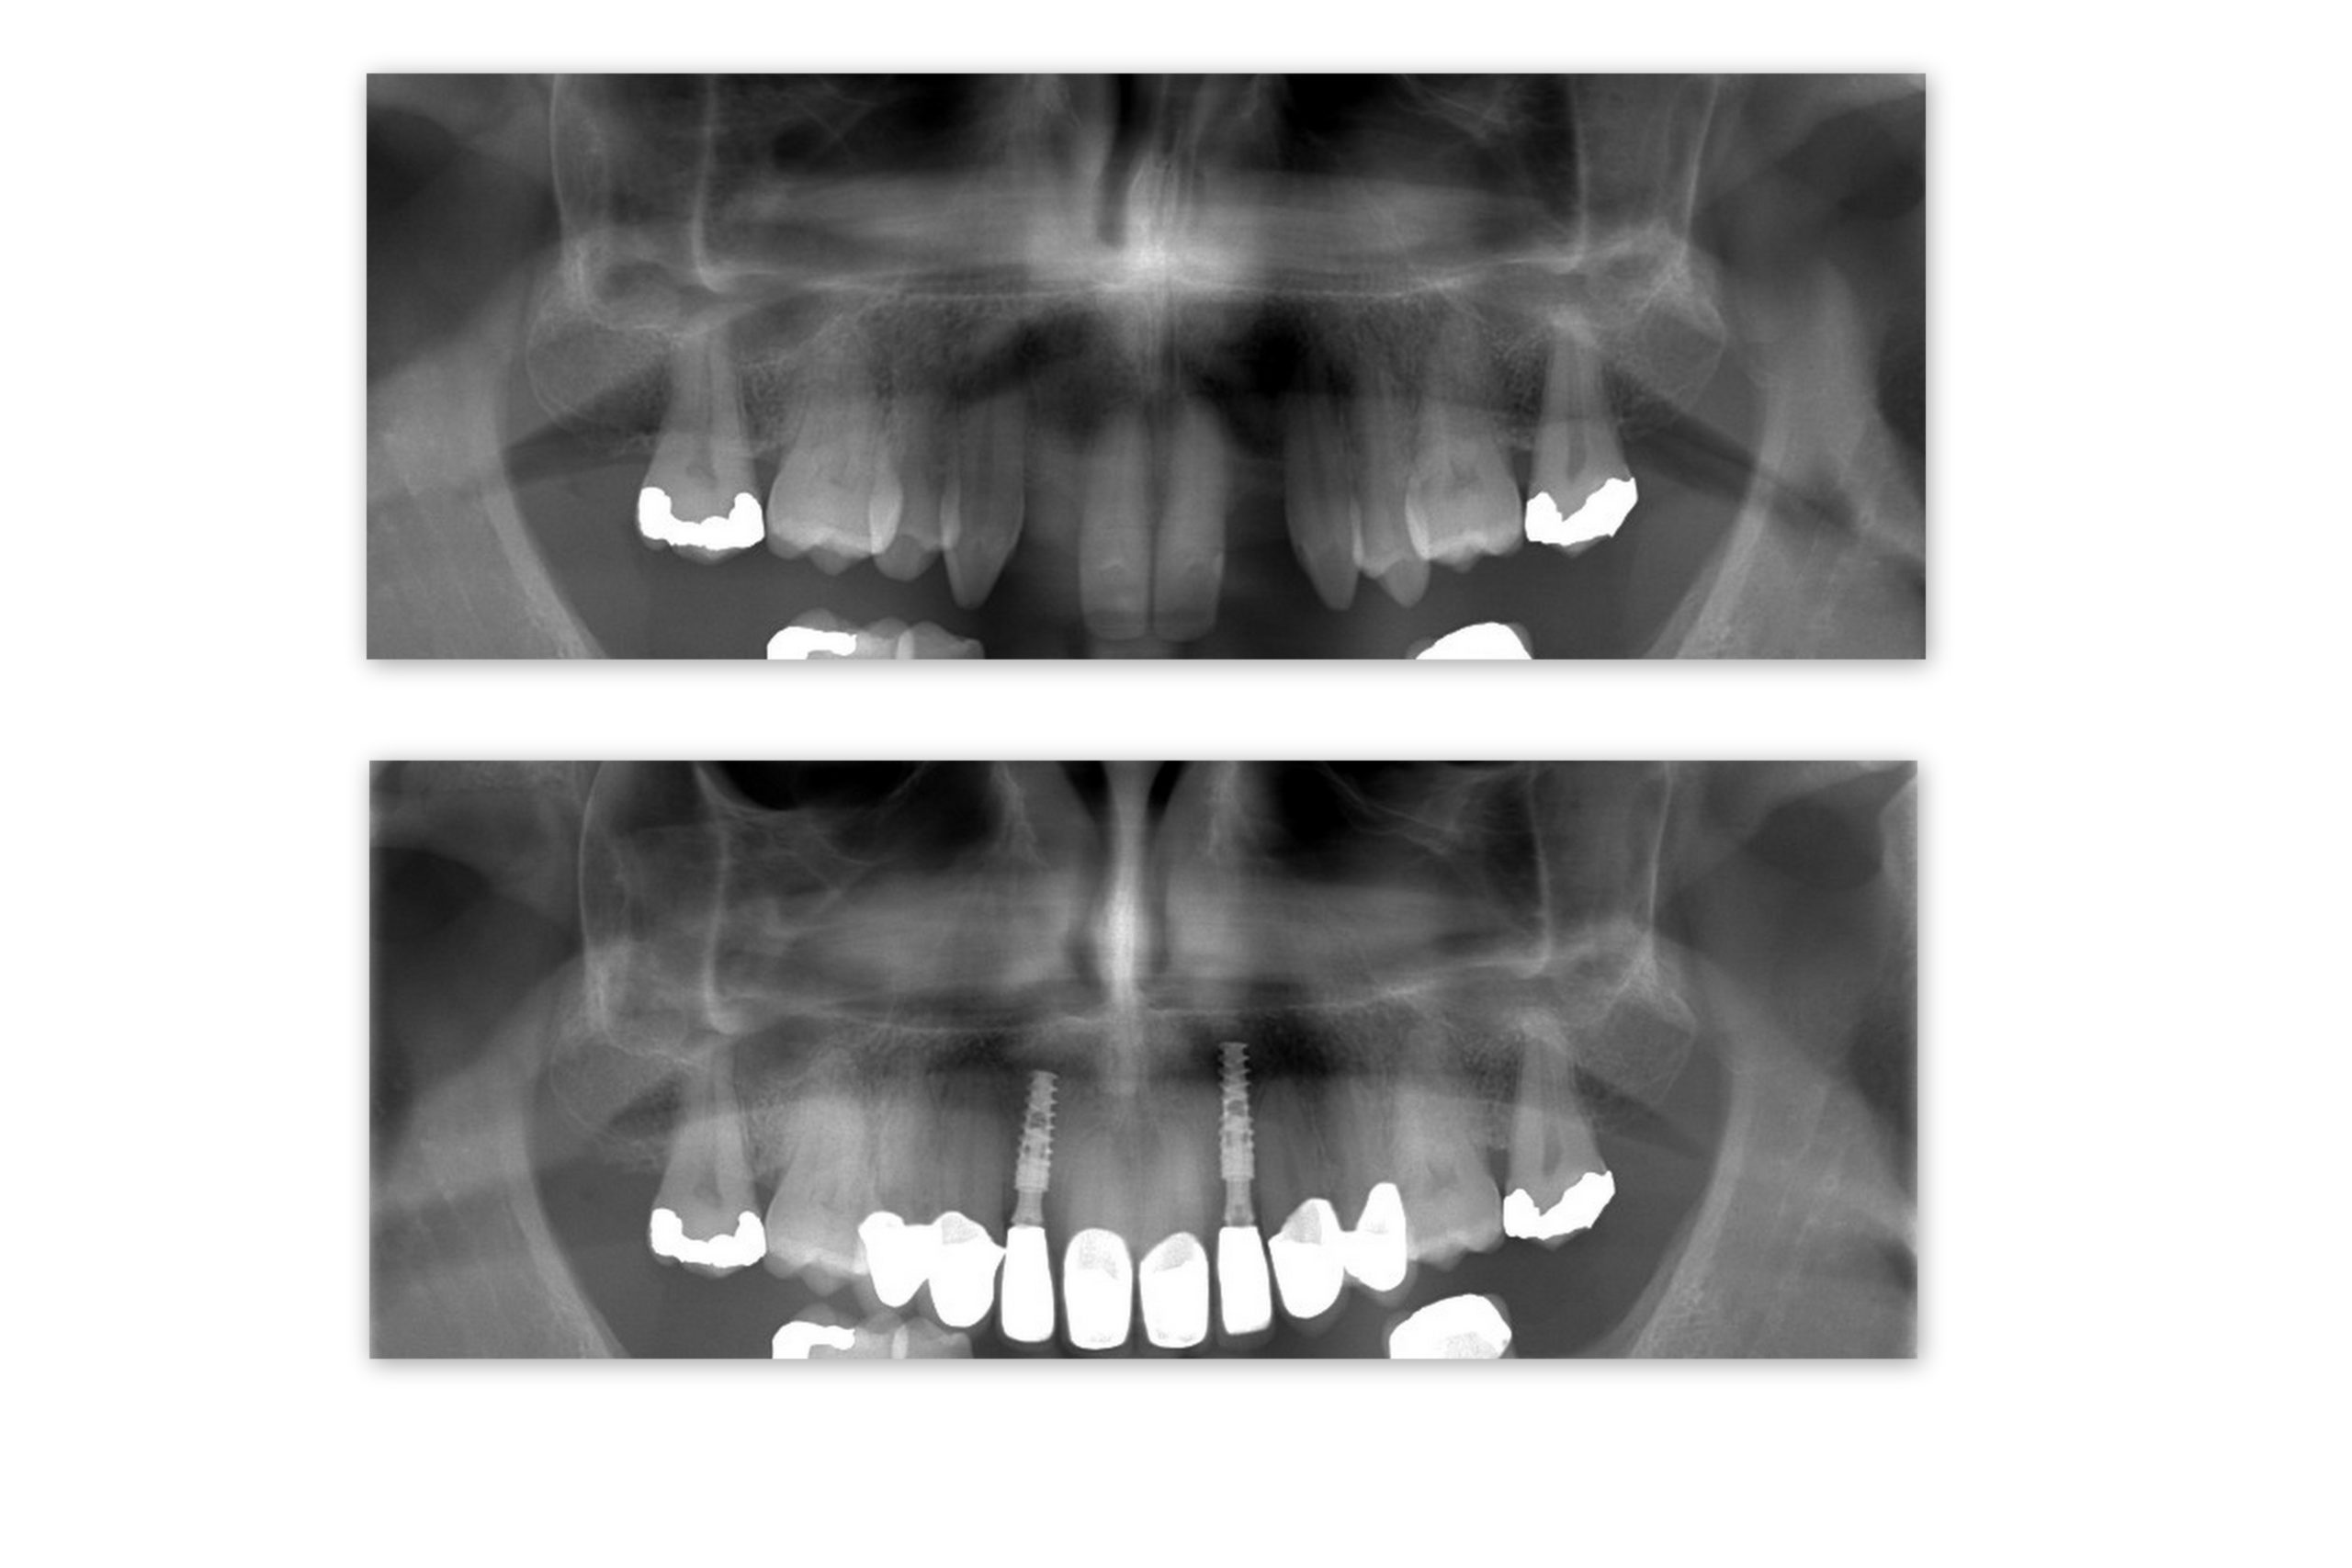

A recent Smile Clinic – Dental Holiday patient, Karl, was born with condition called hypodontia – missing teeth. Karl was given a retainer as a teenager and he got used to wearing it. But now in his 30’s, Karl said to himself, it is time to fix your missing teeth. So, he got rid of the retainer with dental implants. He had two implants with zirconium crowns to complete his new Hollywood look 🙂

We were excited to help Karl obtain the smile he always wanted so he didn’t have to wear a retainer the rest of his life. Karl came with his father (who also had dental treatment). They were both happy with the experience and enjoyed their stay in the spa town of Piešťany where one of Smile Clinic Slovakia treatment center is located.